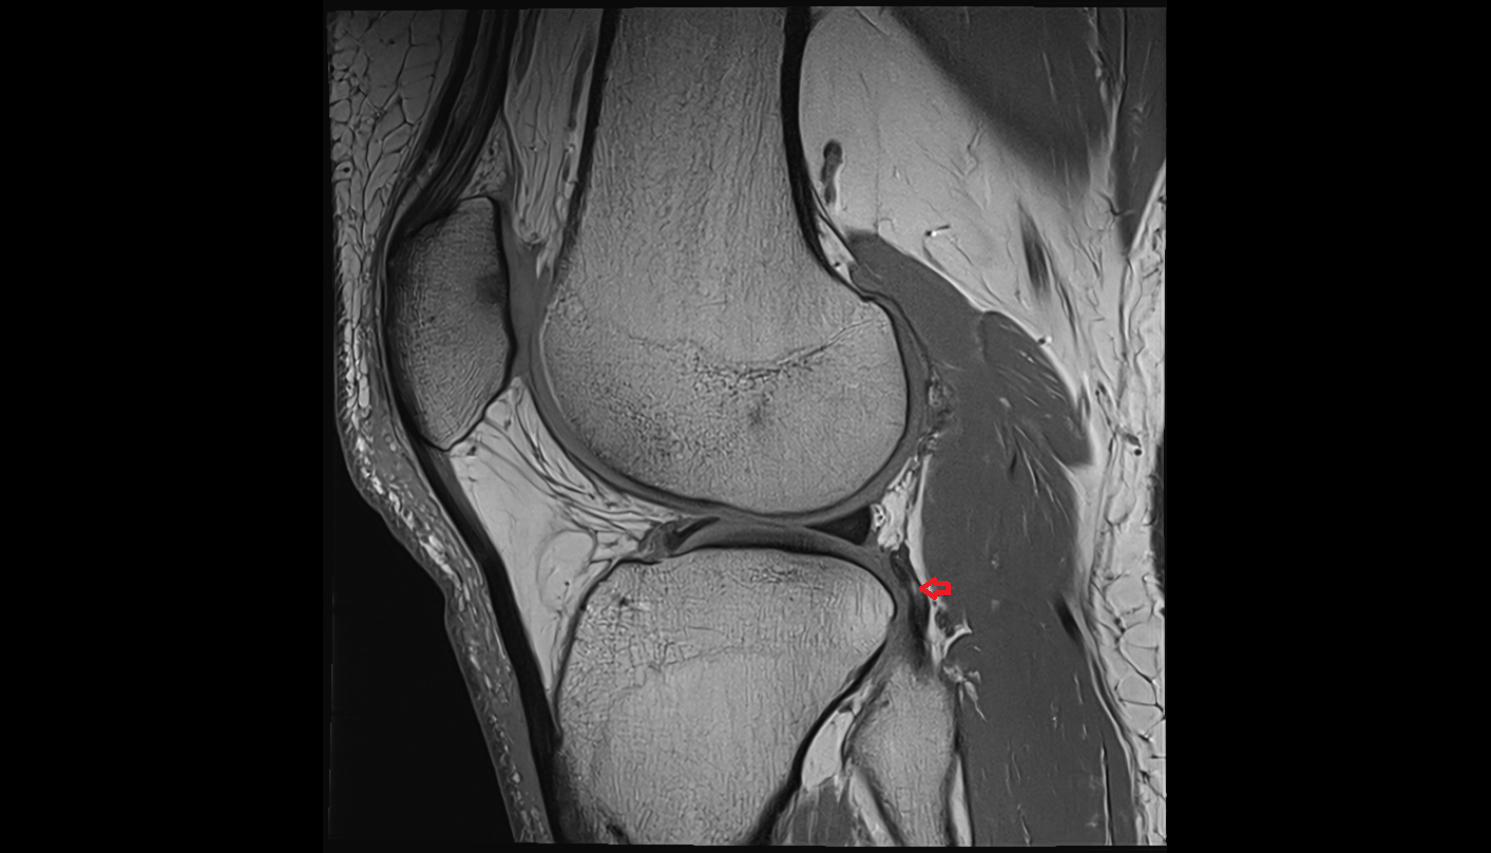

- Medial meniscus

- Posterior horn of medial meniscus

- Lateral meniscus

- Posterior horn of lateral meniscus